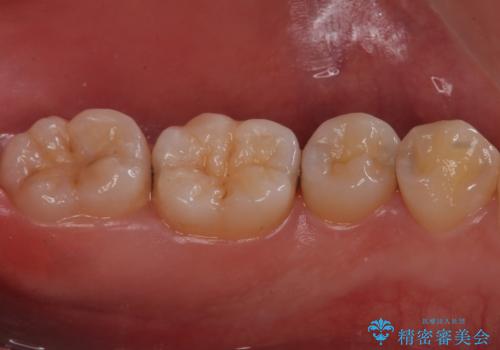

歯と歯の間の虫歯 セラミックインレーでの治療

歯と歯の間に虫歯があったため適合の良いセラミックインレーで修復処置をしていきました。

- 左下567 セラミックインレー 77,000円×3本費用は治療当時の料金となります

歯と歯の間は虫歯の好発部位となっています。

適合の良いインレーでの修復により再発のリスクを下げることができます。